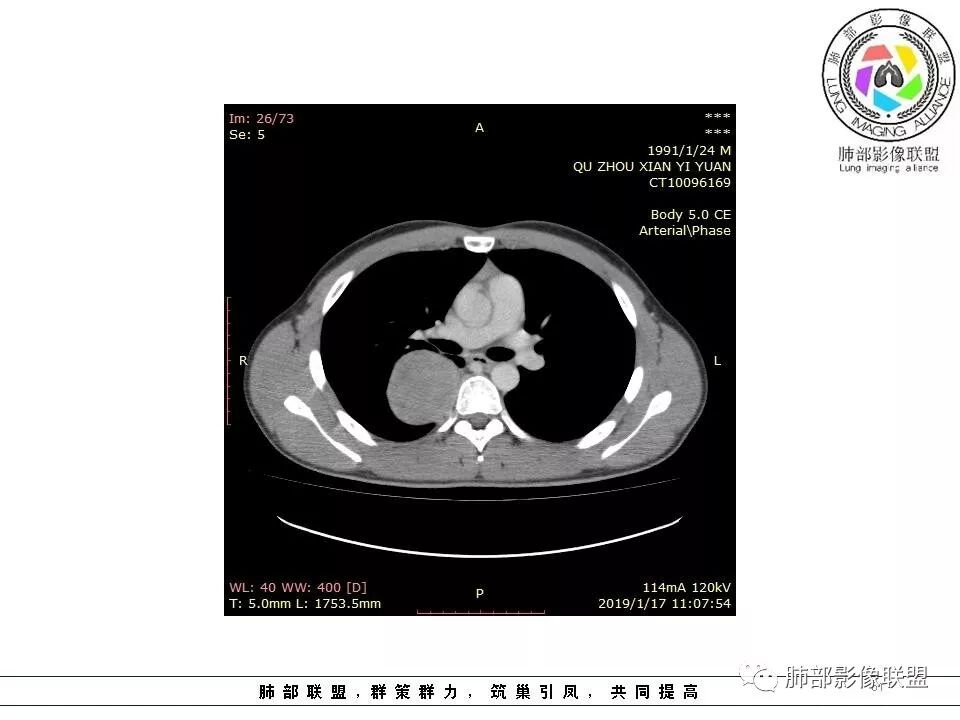

大家说的,大多数意见都很一致,我就不重复了,我说一下我看的这个细节,我觉得这个是壁层胸膜的强化。肿块位于脏层胸膜上,积液在强化的壁层胸膜内,所以我觉得这个首先还是考虑孤立性纤维瘤。

边缘光滑,宽基底与胸壁相连,跨叶裂,叶裂稍前推,血管、支气管前移。

浅分叶

外上侧少量胸水

肋间动脉供血,强化尚均匀,逐步强化

如果一个大的病变,无论胸膜腔内、还是外,它都会将液体局部阻断,因为太大会把局部隆起,胸膜局部推压,哪一方面推压都会阻断。如果幸运看到里面的积液,积液可见渗入到附近间隙,如果在肿块后面肯定是胸膜腔内,在前面,要么是壁层胸膜,要么胸膜外的。

1.右上胸内脊柱旁类圆形肿块,质地似乎比较坚实,密度稍显不均,但未显示明确的坏死。

如此密度形态的病灶位于肺边缘首先应当想到孤立性纤维瘤,可相邻胸膜未见明显的异常强化和胸膜方向延伸。

2.肋间动脉病供血也提示肿块来自后纵隔?